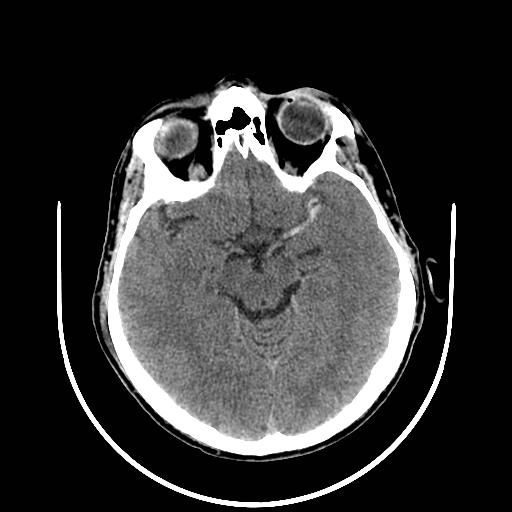

脑动脉高密度征(动脉致密征)

此征象出现时间最早(高级考点),发病1小时内就可出现。其表现为病变同侧M1段呈现条状高密度影,M2或M3处出现点状高密度点。不过,该征象的出现概率较低,容易发生漏诊情况。为进一步确认,可借助 CTA 来证实相应动脉是否闭塞。